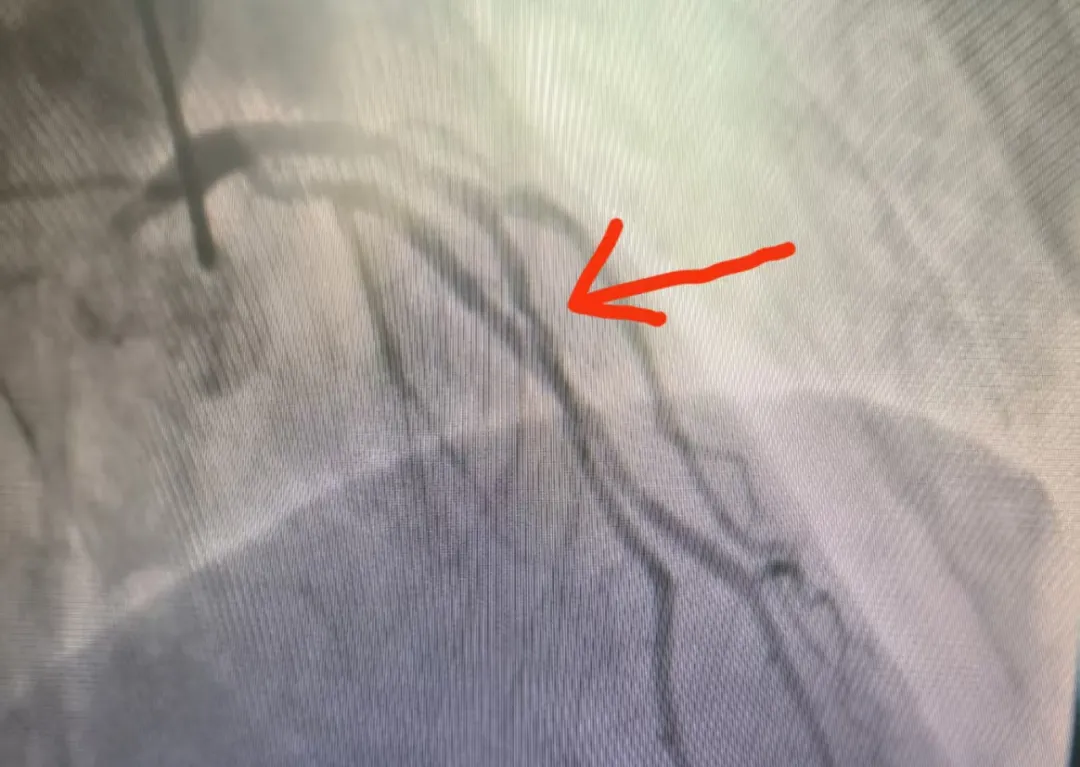

心血管疾病是威脅人類健康的“頭號(hào)殺手”,葫蘆島市第二人民醫(yī)院中醫(yī)科王崇權(quán)主任團(tuán)隊(duì)在不斷努力下,找到了新的破解之道。王崇權(quán)主任團(tuán)隊(duì)深諳“整體觀念、辨證論治”的中醫(yī)精髓,巧妙地將傳統(tǒng)中醫(yī)藥智慧與現(xiàn)代醫(yī)學(xué)技術(shù)相結(jié)合,在心血管危重癥干預(yù)領(lǐng)域取得了令人矚目的突破,為患者開辟了一條獨(dú)具特色的康復(fù)之路。 神奇療效,見證中醫(yī)力量 心血管疾病作為慢性疾病,病情遷延,復(fù)發(fā)率較高,聯(lián)合中醫(yī)藥的治療,可以取得顯著的效果。特別是在冠心病、心律失常、心衰、高血壓、失眠、焦慮、便秘、痛癥、體重管理等方面,尤為明顯。 病例一:頑固性早搏患者經(jīng)中藥調(diào)理1個(gè)月,24小時(shí)動(dòng)態(tài)心電圖顯示早搏次數(shù)從34061次降至153次,睡眠質(zhì)量與精神狀態(tài)同步改善。 5月10日數(shù)據(jù) 7月1日數(shù)據(jù) 病例二:47歲心梗后心衰患者,在西醫(yī)規(guī)范治療基礎(chǔ)上配合中藥湯劑,心臟射血分?jǐn)?shù)(EF值)從34%提升至50%,胸悶、氣短等癥狀明顯改善。 5月16日數(shù)據(jù) 7月1日數(shù)據(jù) 病例三:58歲男性反復(fù)胸痛,冠脈造影顯示前降支中段重度狹窄(70%),經(jīng)三個(gè)月中藥治療后復(fù)查冠脈CT,狹窄程度減輕為輕度(30%)。 治療前造影 治療后診斷結(jié)果 病例四:46歲男性,反復(fù)胸痛伴焦慮狀態(tài),湯藥治療后胸痛明顯緩解,復(fù)查冠脈較前明顯改善。 治療前 治療后 這四個(gè)典型病例充分展示了中醫(yī)藥在心血管疾病防治中的獨(dú)特優(yōu)勢(shì)。這種源于傳統(tǒng)醫(yī)學(xué)的整體調(diào)理理念,不僅針對(duì)病癥本身進(jìn)行治療,更注重恢復(fù)機(jī)體的陰陽(yáng)平衡,激發(fā)自身的修復(fù)能力,為心血管疾病患者提供了特色鮮明的治療選擇。 葫蘆島市第二人民醫(yī)院中醫(yī)科在王崇權(quán)主任的帶領(lǐng)下,持續(xù)深入挖掘中醫(yī)藥寶庫(kù),致力于在心血管疾病防治領(lǐng)域開展更多的臨床實(shí)踐與研究,為提升人類健康水平貢獻(xiàn)中醫(yī)智慧。 中醫(yī)科簡(jiǎn)介 葫蘆島市第二人民醫(yī)院中醫(yī)科集中醫(yī)預(yù)防、治療、康復(fù)、保健于一體,以深厚的中醫(yī)藥文化為底蘊(yùn),秉承“整體觀念,辨證論治”的核心思想,運(yùn)用傳統(tǒng)中醫(yī)理論和方法,結(jié)合現(xiàn)代醫(yī)學(xué)技術(shù),為患者提供優(yōu)質(zhì)中醫(yī)診療服務(wù)。 運(yùn)用中藥飲片、顆粒、膏方、針灸、推拿、拔罐、中藥外敷、刮痧、穴位貼敷、耳穴壓豆等多種方法辨證施治,針對(duì)不同病癥的病因病機(jī),精準(zhǔn)調(diào)節(jié)臟腑功能,實(shí)現(xiàn)內(nèi)外兼治,標(biāo)本兼顧。 1、內(nèi)科疾病調(diào)治 高血壓、冠心?。ㄐ慕g痛)、心律失常、PCI術(shù)后康復(fù)、慢性疼痛、頑固性失眠、頭痛眩暈、疲勞綜合征及免疫力調(diào)節(jié)等。 2、亞健康狀態(tài)干預(yù) 基于中醫(yī)體質(zhì)辨識(shí)(氣虛/陽(yáng)虛/陰虛/痰濕/濕熱等),針對(duì)性調(diào)理慢性疲勞、睡眠障礙、焦慮狀態(tài)及體質(zhì)偏頗。 3、腫瘤輔助療法 緩解放化療副作用(消化道反應(yīng)、骨髓抑制、癌因性疲乏),協(xié)同增強(qiáng)免疫功能,改善生存質(zhì)量。 4、精準(zhǔn)體重管理 融合體質(zhì)辨證(BMI/體脂分析)、中藥內(nèi)調(diào)(代茶飲/膏方)、外治療法(針灸/穴位埋線/雷火灸)及個(gè)性化運(yùn)動(dòng)膳食指導(dǎo),構(gòu)建科學(xué)減重體系。 人民醫(yī)院 人民名醫(yī) 王崇權(quán) 副主任中醫(yī)師 碩士研究生 ·葫蘆島第二人民醫(yī)院心臟中心門急診主任、中醫(yī)科主任 ·國(guó)家中醫(yī)藥管理局龍砂醫(yī)學(xué)流派五運(yùn)六氣第四批傳承人 ·全國(guó)醫(yī)藥技術(shù)市場(chǎng)協(xié)會(huì)心衰防治專業(yè)委員會(huì)委員 ·中國(guó)醫(yī)藥信息學(xué)理事會(huì)心力衰竭學(xué)術(shù)委員會(huì)委員 ·中國(guó)民族醫(yī)藥學(xué)會(huì)委員 ·遼寧省中西醫(yī)介入委員會(huì)常務(wù)委員 ·葫蘆島醫(yī)學(xué)會(huì)心血管病分會(huì)委員 ·葫蘆島醫(yī)學(xué)會(huì)心電生理與起搏學(xué)會(huì)分會(huì)委員 ·葫蘆島市醫(yī)學(xué)會(huì)急診醫(yī)學(xué)分會(huì)委員 專業(yè)特色:師從遼寧中醫(yī)藥大學(xué)附屬醫(yī)院知名專家張明雪教授,從事臨床工作10余年,擅長(zhǎng)胸痹、心悸、喘證、失眠等疾病的中醫(yī)傳統(tǒng)湯藥治療;中西醫(yī)結(jié)合治療冠心病、心力衰竭、高血壓、心律失常等心血管疾?。恍难芗膊∥V鼗颊叩膿尵燃凹痹\PCI治療等。在涌泉貼、耳穴壓豆、穴位按摩、中藥足浴治療失眠等內(nèi)科疾病方面效果顯著。開設(shè)中醫(yī)減肥門診,中西醫(yī)結(jié)合進(jìn)行系統(tǒng)體重管理。順利完成急性心肌梗死溶栓治療百余例,冠狀動(dòng)脈造影及PCI手術(shù)2000余例,成功搶救危重患者數(shù)百例。 學(xué)術(shù)成就:多次前往北部戰(zhàn)區(qū)總醫(yī)院、遼寧中醫(yī)藥大學(xué)附屬醫(yī)院、大連市友誼醫(yī)院等知名醫(yī)院進(jìn)修學(xué)習(xí),在中西醫(yī)結(jié)合治療心血管疾病領(lǐng)域有所突破。參與編撰書籍《從溫病論治病毒性心肌炎》《 基于網(wǎng)絡(luò)藥理學(xué)探討肺癌培元固本法的用藥規(guī)律研究》《醫(yī)養(yǎng)結(jié)合概論》,發(fā)表《血府逐瘀湯聯(lián)合他汀治療高脂血癥療效分析》《歸脾湯加減結(jié)合降壓藥治療老年性高血壓臨床效果觀察》等多篇文章。參與課題《評(píng)價(jià)祛痰化瘀、益氣溫陽(yáng)法治療冠心病合并緩慢性心律失常的臨床研究》《基于真實(shí)世界的冠心寧片治療穩(wěn)定性冠心病的多中心病例注冊(cè)登記研究》的臨床研究及病例收集分析。主持葫蘆島市課題《中醫(yī)聯(lián)合外治法通過(guò)調(diào)控RASS系統(tǒng)干預(yù)腎陽(yáng)不足型高血壓研究》。 出診時(shí)間: ??健康體重管理門診:每周一上午(門診三樓4號(hào)診室) ??心內(nèi)中西醫(yī)科:每周二上午(心臟門急診4診室) 顧平 主治醫(yī)師 中醫(yī)內(nèi)科學(xué)碩士 ·葫蘆島市第二人民醫(yī)院中醫(yī)科主治醫(yī)師 ·遼寧省中醫(yī)藥學(xué)會(huì)針刀分會(huì)委員 ·江蘇省研究型醫(yī)院學(xué)會(huì)睡眠分會(huì)委員 ·江蘇省中醫(yī)藥學(xué)會(huì)針灸分會(huì)委員 專業(yè)特色:曾于中國(guó)中醫(yī)科學(xué)院西苑醫(yī)院進(jìn)修心血管疾病相關(guān)的中醫(yī)治療。擅長(zhǎng)中醫(yī)辨證方藥治療冠心病、心力衰竭、高血壓、焦慮證、抑郁證;針?biāo)幗Y(jié)合治療失眠癥、脾胃??;針灸治療頸肩腰腿痛;針灸美容及代謝綜合征的體重管理。先后發(fā)表5篇核心期刊論文。主持課題“加味二仙湯治療陰虛陽(yáng)亢型高血壓病的血漿代謝組學(xué)研究”一項(xiàng)。參與編著《中醫(yī)藥治療病毒性心肌炎》和《冠心病證候研究》兩部著作。